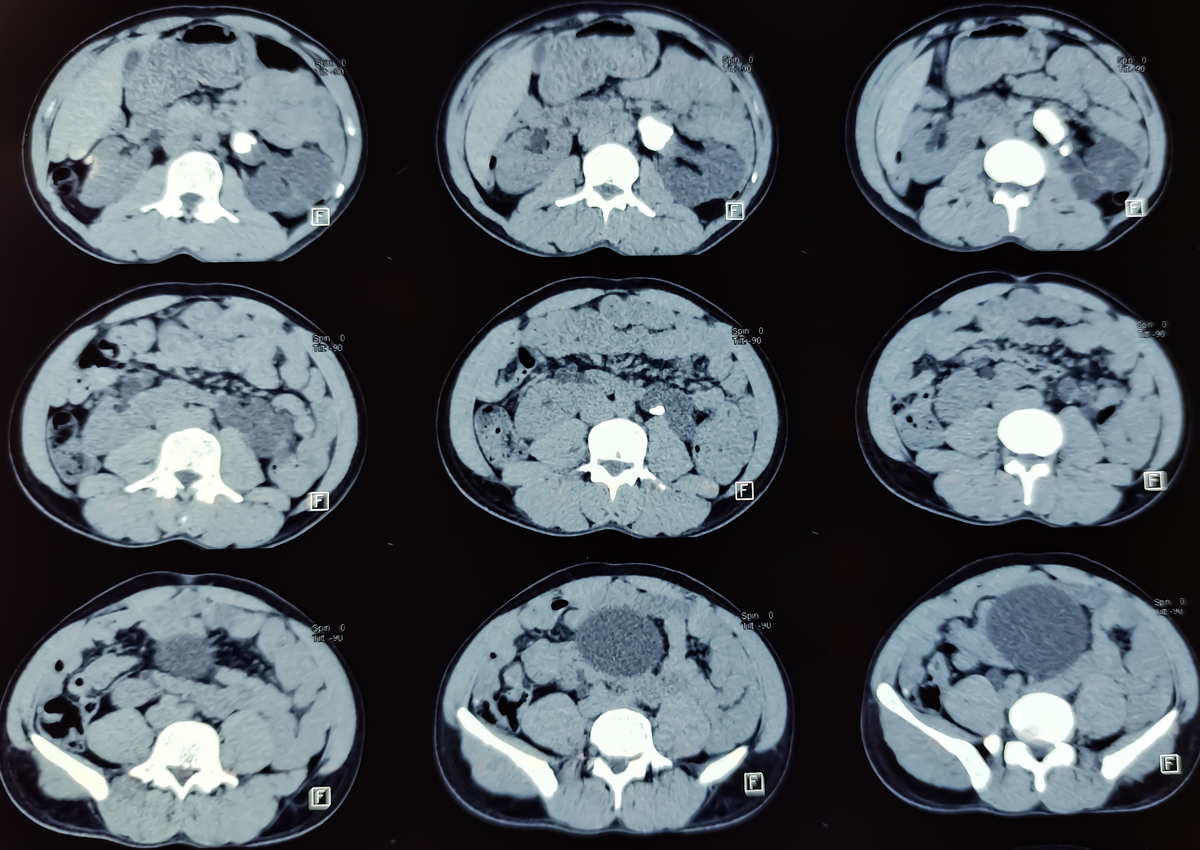

钆造影剂是一种含有重金属钆的造影剂,通常用于医学影像学检查中。钆造影剂在进入人体后会被肾脏、肝脏等器官过滤和排泄,但其分子结构较大,容易在肾脏小管内积聚,对肾脏造成一定程度的损伤。此外,钆造影剂也会影响肝脏的代谢和排泄功能,导致肝脏负担加重,可能引起肝脏损害。

具体来说,钆造影剂的原理是通过吸收X射线或磁场等电磁波来产生影像。在进入人体后,钆造影剂会被血液循环到需要检查的器官,然后被这些器官吸收和分布。在影像检查过程中,钆造影剂会减少X射线或磁场的穿透能力,从而形成对比度明显的影像。然而,钆造影剂的过程也会对肾脏和肝脏造成一定的负担和损伤,尤其是对于肾功能不全或肝功能受损的患者,更容易出现不良反应。因此,在使用钆造影剂时需要注意剂量和使用方法,以减少对肾脏和肝脏的损害。

钆造影剂损伤肾脏和肝脏损害的原理